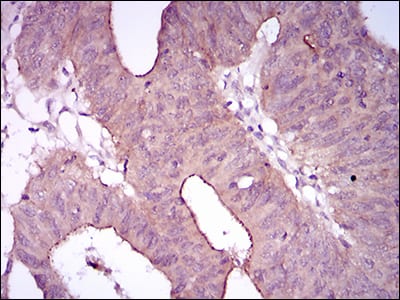

分类: 科研抗体货号: 30506别名: SCS; ACS3; CRS1; BPES2; BPES3; TWIST; bHLHa38应用: WB,IHC,IF,FCM反应种属: Human,Mouse,Rat,Rabbit